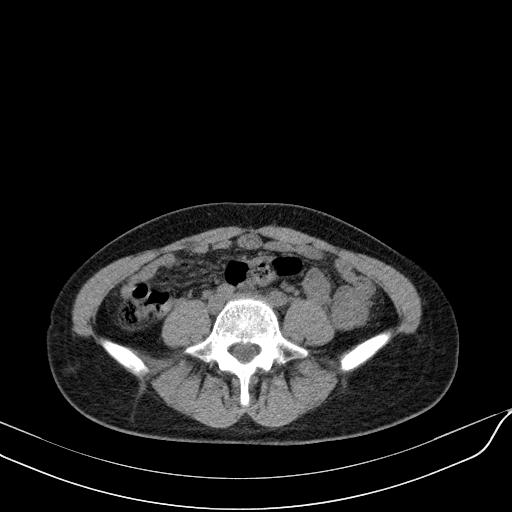

标题: CT23965:无外伤史,下腹痛 [打印本页]

标题: CT23965:无外伤史,下腹痛

无外伤史,下腹部疼痛!---------正常

肠道未准备,继续往下扫,乙状结肠占位不排除。建议钡灌或结肠镜检查。

乙状结肠占位不排除

未见明显异常改变,做个气钡双重造影除外一下结肠病变,无外伤史为啥不常规喝泛影葡胺水对比剂再扫ct呢?

回肠间质瘤?

肠道肿瘤,建议行钡剂灌肠检查。